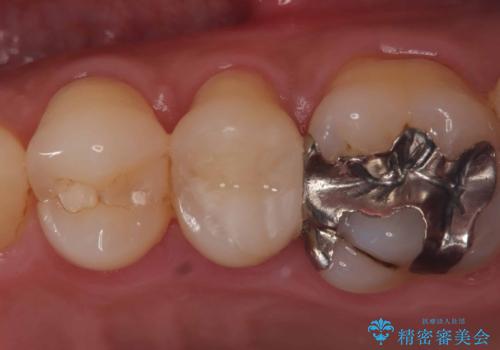

- 当院にて根管治療を行いましたが、病変の改善が得られなかったため、インプラント治療を行う方針といたしました。

抜歯即時埋入の適応と判断し、抜歯当日にインプラント埋入を行う「抜歯即時埋入」にて処置を実施しました。

●低侵襲

抜歯窩を利用してインプラントを埋入するので、歯茎を切る必要が無く術後の痛みが出にくい